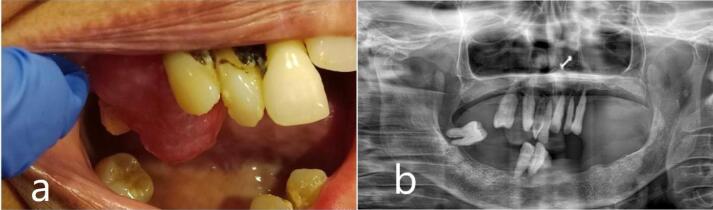

Oral Focal Mucinosis.